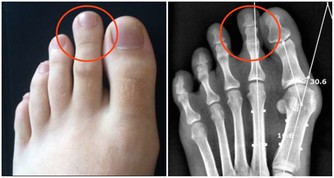

這種方法可以使意念集中,將人體的氣血引向足底,對於高血壓、糖尿病、頸腰椎病等諸多疑難病都有立竿見影的療效,還可以治療小腦萎縮,並可預防美尼爾、痛風等許多病症。

對於足寒症更是效果奇佳,這是治本的方法,可以迅速地增強人體的免疫力。